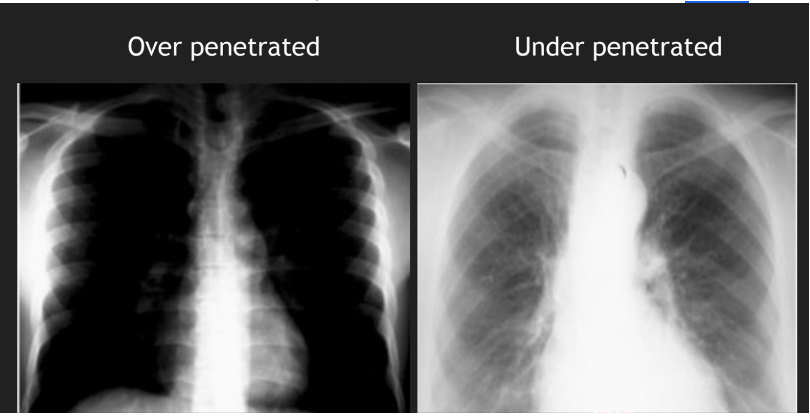

4

Q

Exposure

A

can you see vertebrae behind heart